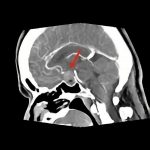

断層撮影